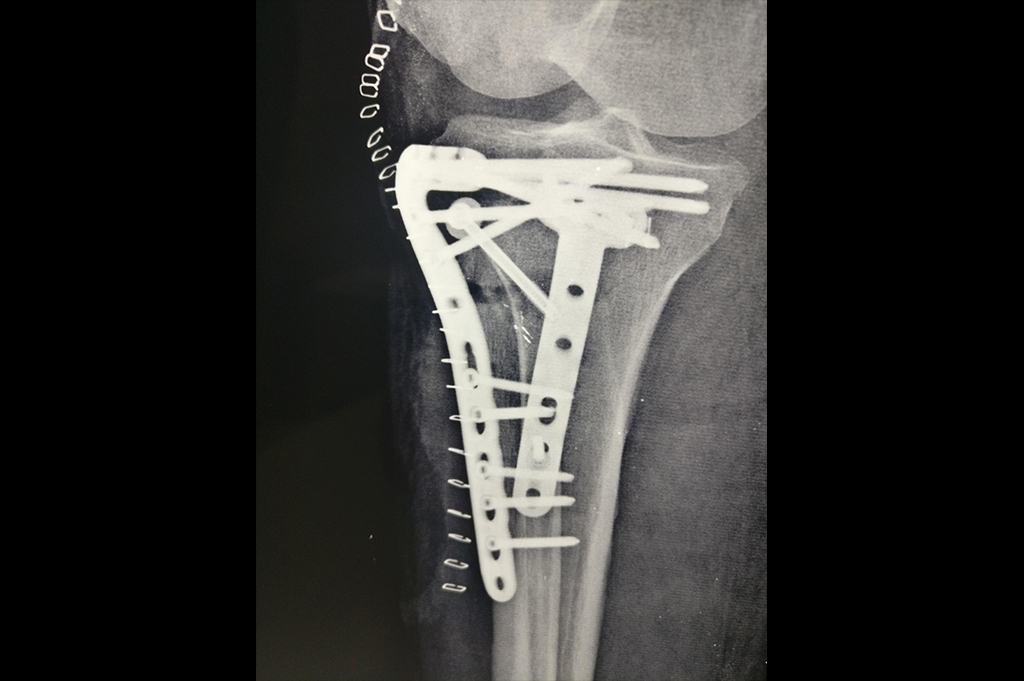

Periprosthetic Fracture THR